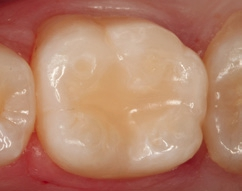

Die Weiterversorgung erfolgte nach adhäsiver Vorbehandlung mit einem approximal eingebrachten 4-mm-Inkrement SDR flow+ (Dentsply Sirona) in der Farbe A3, klassisch überschichtet mit ceram.x universal in der Farbe A3,5. Die Wahl auf ein Bulk-Flow-Komposit approximal fiel aufgrund der optimalen selbstnivellierenden Adhäsion zum Adhäsiv und somit zur Reduktion potenzieller Fehlerquellen in der Schichttechnik, die Wahl zugunsten des eingefärbten SDR flow+ in der Farbe A3 entgegen der transluzenten Universalfarbe U aufgrund der im Approximalraum dunkel erscheinenden Gold-Restauration am Nachbarzahn. Dies ergab in der Vergangenheit bei Verwendung von SDR flow+ U oft ein unschönes „grau-transluzent“ erscheinendes Bild der Kompositrestauration im Approximalraum. Ästhetisch störte dies meist nur bedingt, suggerierte aber immer die latente Möglichkeit einer Approximalkaries. Durch die Verwendung der Farbe A3 bei SDR flow+ war ein derartiges grau-transluzentes Erscheinungsbild nicht mehr gegeben; die Restauration erscheint homogener (Abb. 5). Die Abbildung 6 zeigt die Röntgenkontrollaufnahme nach einem Jahr, die Abbildung 7 die klinische Situation: Der Zahn ist weiterhin vital, symptomlos und beschwerdefrei. Direkte Kompositrestaurationen stellen heute gerade bei vorangegangenen Goldinlay-Kavitäten die suffizienteste Sekundärversorgung dar: Der vorhandene Federrand kann belassen werden und muss nicht in eine plane Stufe einer Keramikrestauration umpräpariert werden.

Im Röntgenbild ist kein Unterschied in der Röntgenopazität zwischen SDR flow+ und ceram.x universal auszumachen, obwohl 2/3 der approximalen Kavitätentiefe von SDR flow+ ausgefüllt wird. Da hinsichtlich ihres Indikationsspektrums direkte Kompositrestaurationen eine ideale Alternative zu Inlayversorgungen darstellen und zudem substanzschonender sowie kosteneffizienter sind, bleibt heute kaum mehr eine wahre Indikation für Inlayversorgungen. Klinisch bewährt hat sich die direkte Kompositversorgung gerade bei dem Austausch kleinerer Goldinlays [13,14].